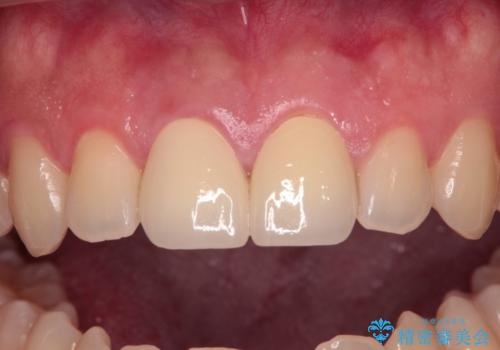

幸いにも神経組織に影響はなく、健全な状態で治療を終えることができました。

歯肉の腫脹が目立っていたため、衛生指導も並行して行い、引き締まった歯肉になりました。

外傷歯は、将来的に歯根吸収を起こす可能性があるため、定期的なレントゲン撮影により経過観察が必要となります。